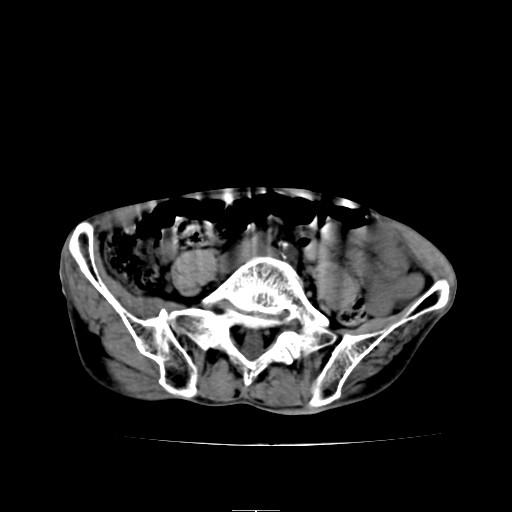

CT50835:外伤24小时。

麻烦各位老师帮我看一下,谢谢!

左侧臀中肌萎缩。

左侧股骨上段周围皮下软组织内见囊性稍高密度影,急性皮下血肿考虑。建议治疗后复查!

左侧臀中肌变形萎缩 钙化